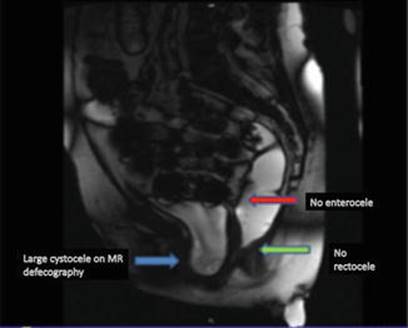

MRI revealed a minimal vault descent and no posterior compartment defect, specifically no enterocele or rectocele (Fig. 16.2). No SUI with or without packing, or detrusor overactivity (DO) was evidenced during UDS. During pressure-flow study, a prolonged flow curve with low maximum flow at 10 mL/s along with Valsalva efforts was noted, with normal range voiding pressures.

Fig. 16.2

MR defecography (T2) confirming anterior compartment defect